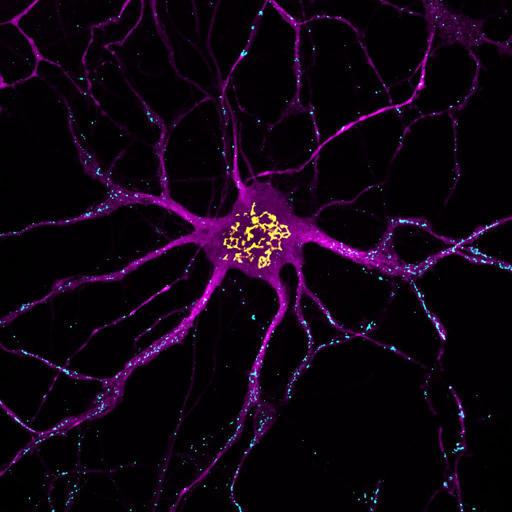

New research from the AIBN has revealed that neurons in the brain use fats for energy, challenging decades of scientific thinking and opening the door to new treatments for neurological disease.